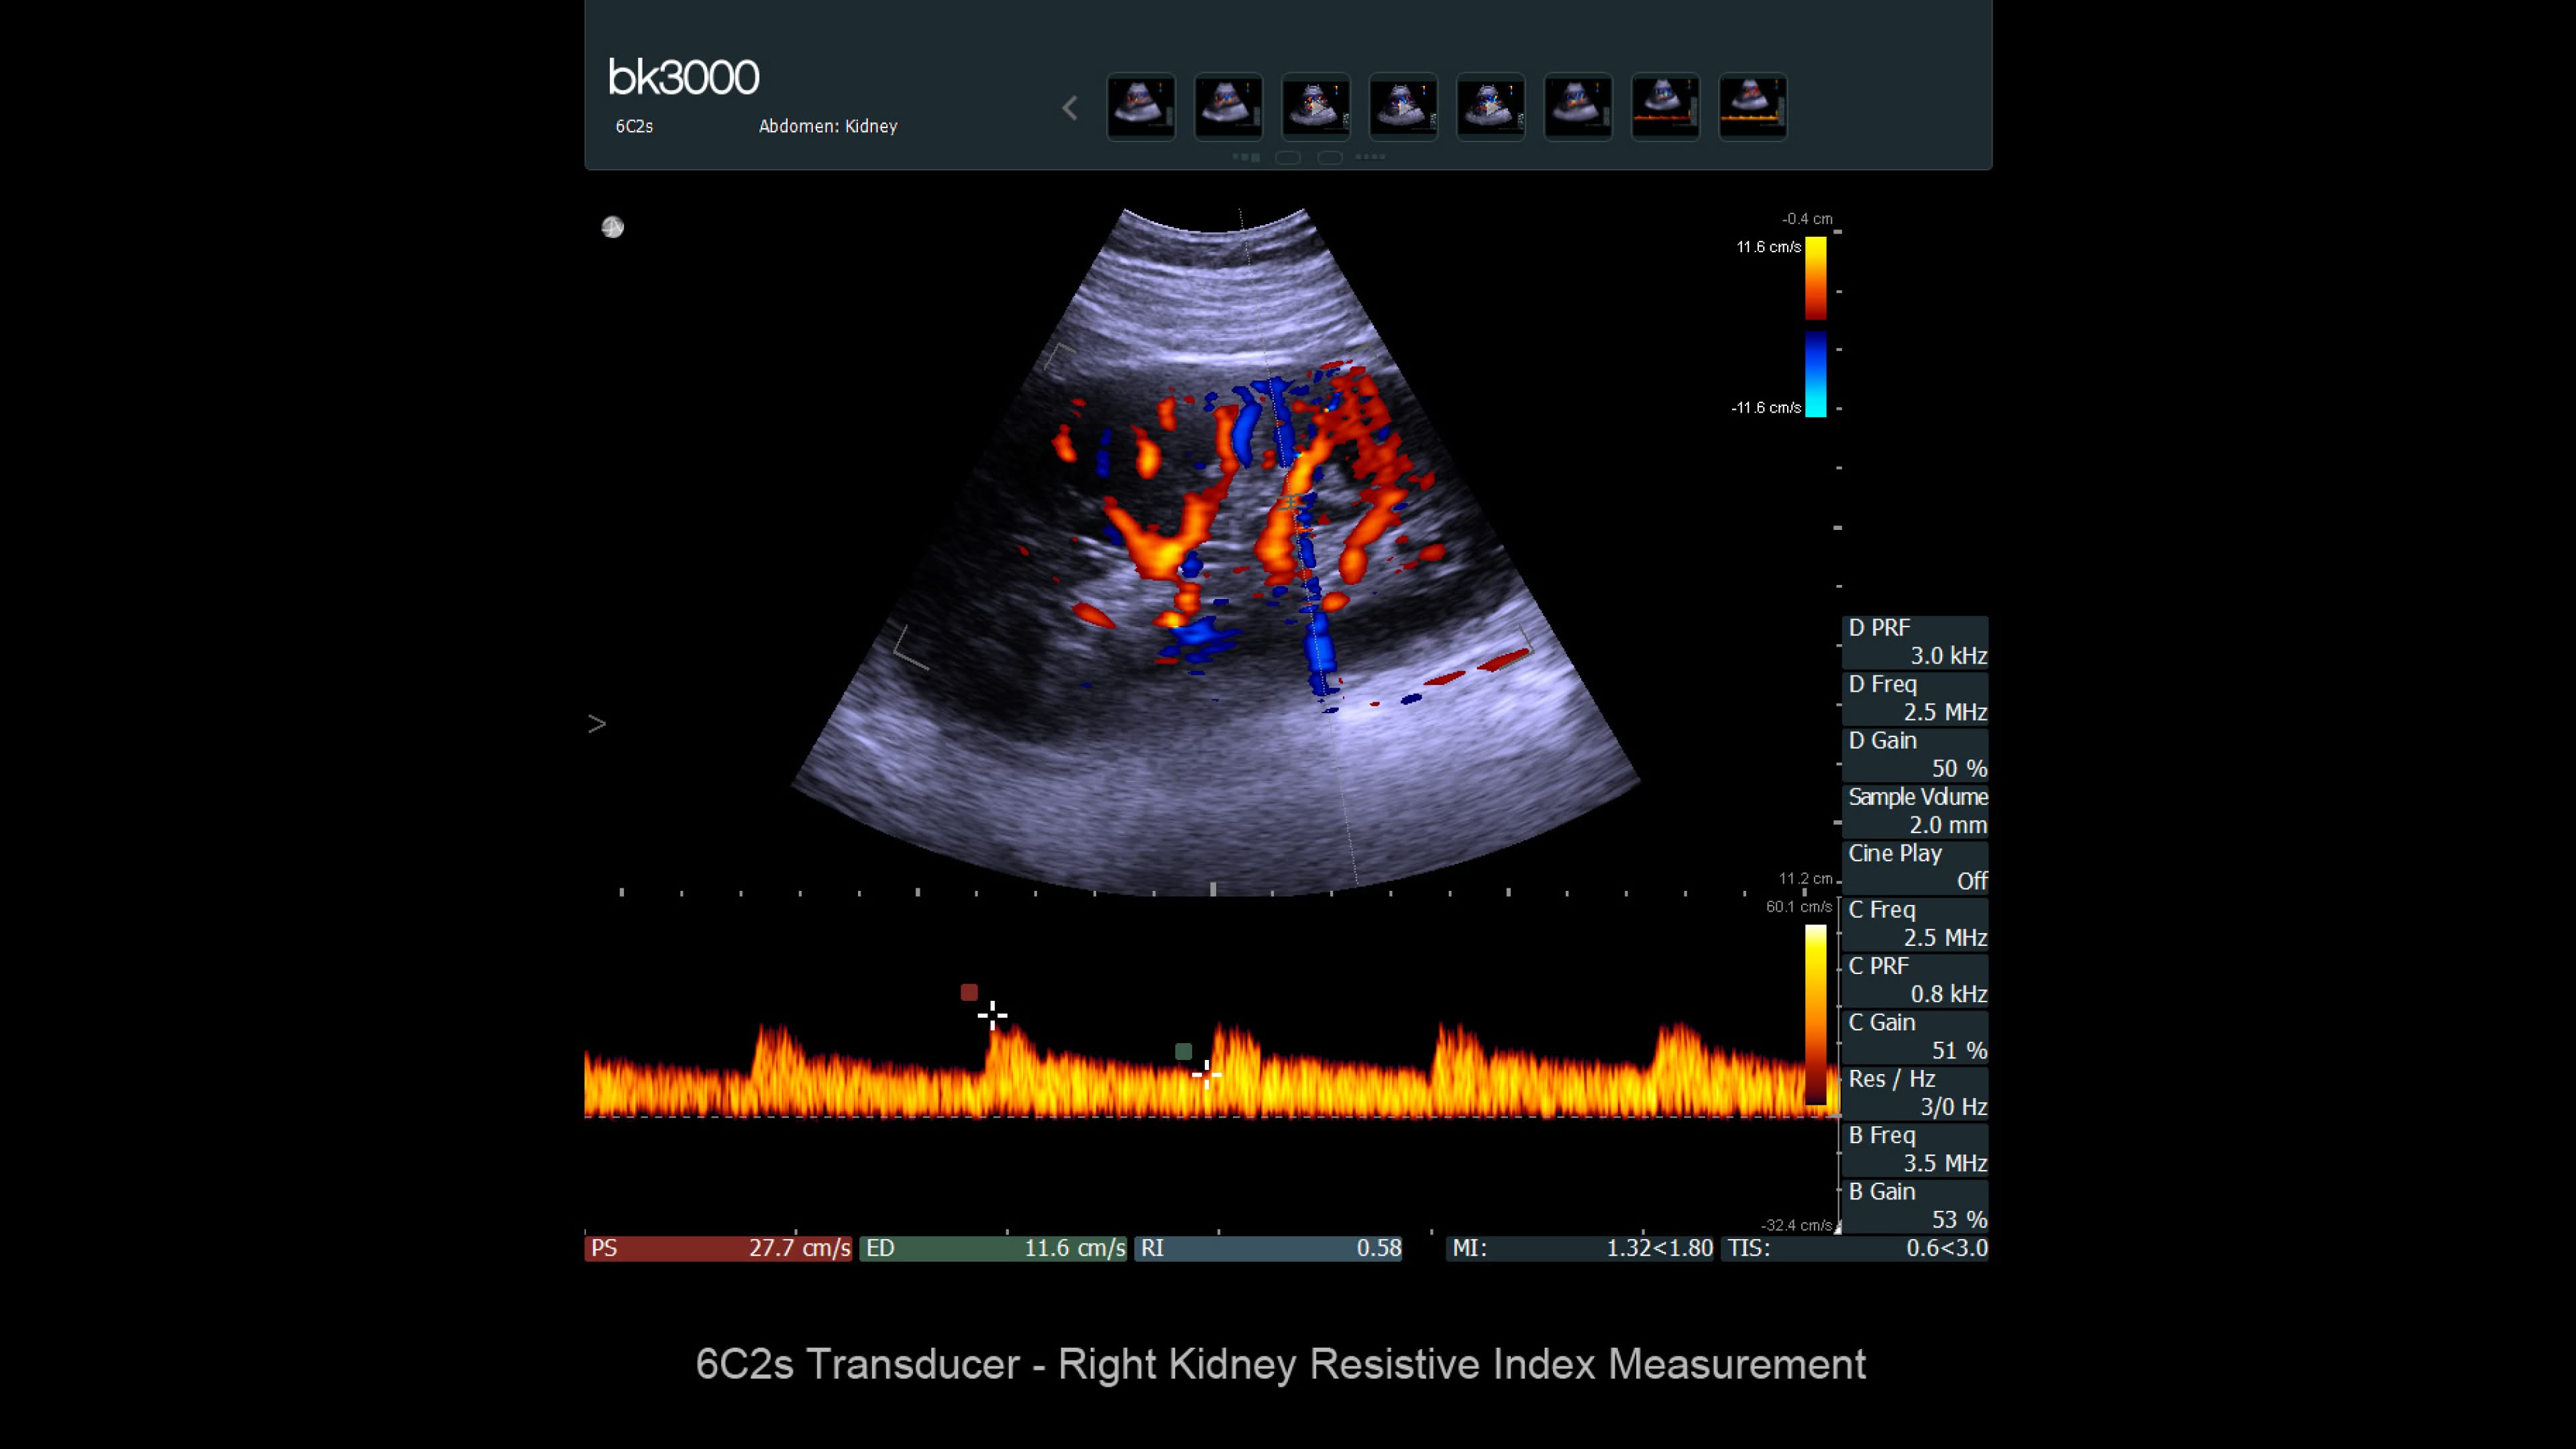

Ultrasound for kidney

Ultrasound provides detailed information for kidney imaging, measurement, and biopsies. The bk3000 and bkSpecto systems help visualize fine anatomical details, see vascularization, measure blood flow, and locate kidney stones. The bkActiv, our flagship system, offers next-level imaging for prostate, renal, kidney, and bladder imaging, with sensitive Doppler for blood flow. Combined with sterilizable transducers, the bkActiv sets a new standard for surgical urology.